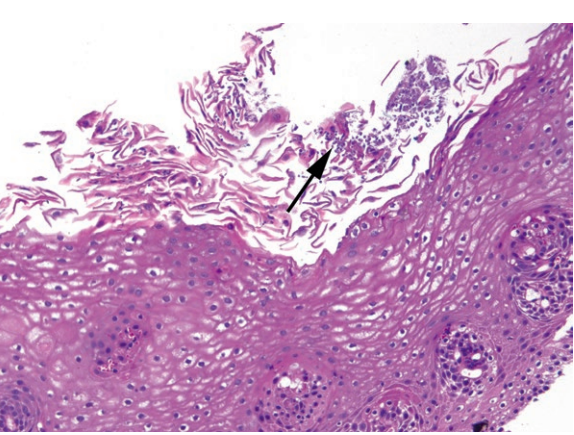

Candida. Tiny purple yeasts and pseudohyphae (arrow) are seen among the squamous debris at the surface of the epithelium. This is an H&E stain; the yeasts are magenta on PAS stain. Note that sometimes there is not a significant neutrophilic response.